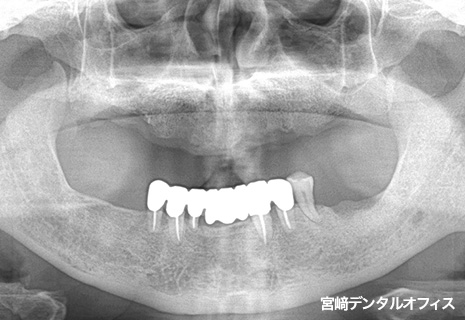

全顎的治療

術前

術後

インプラント治療